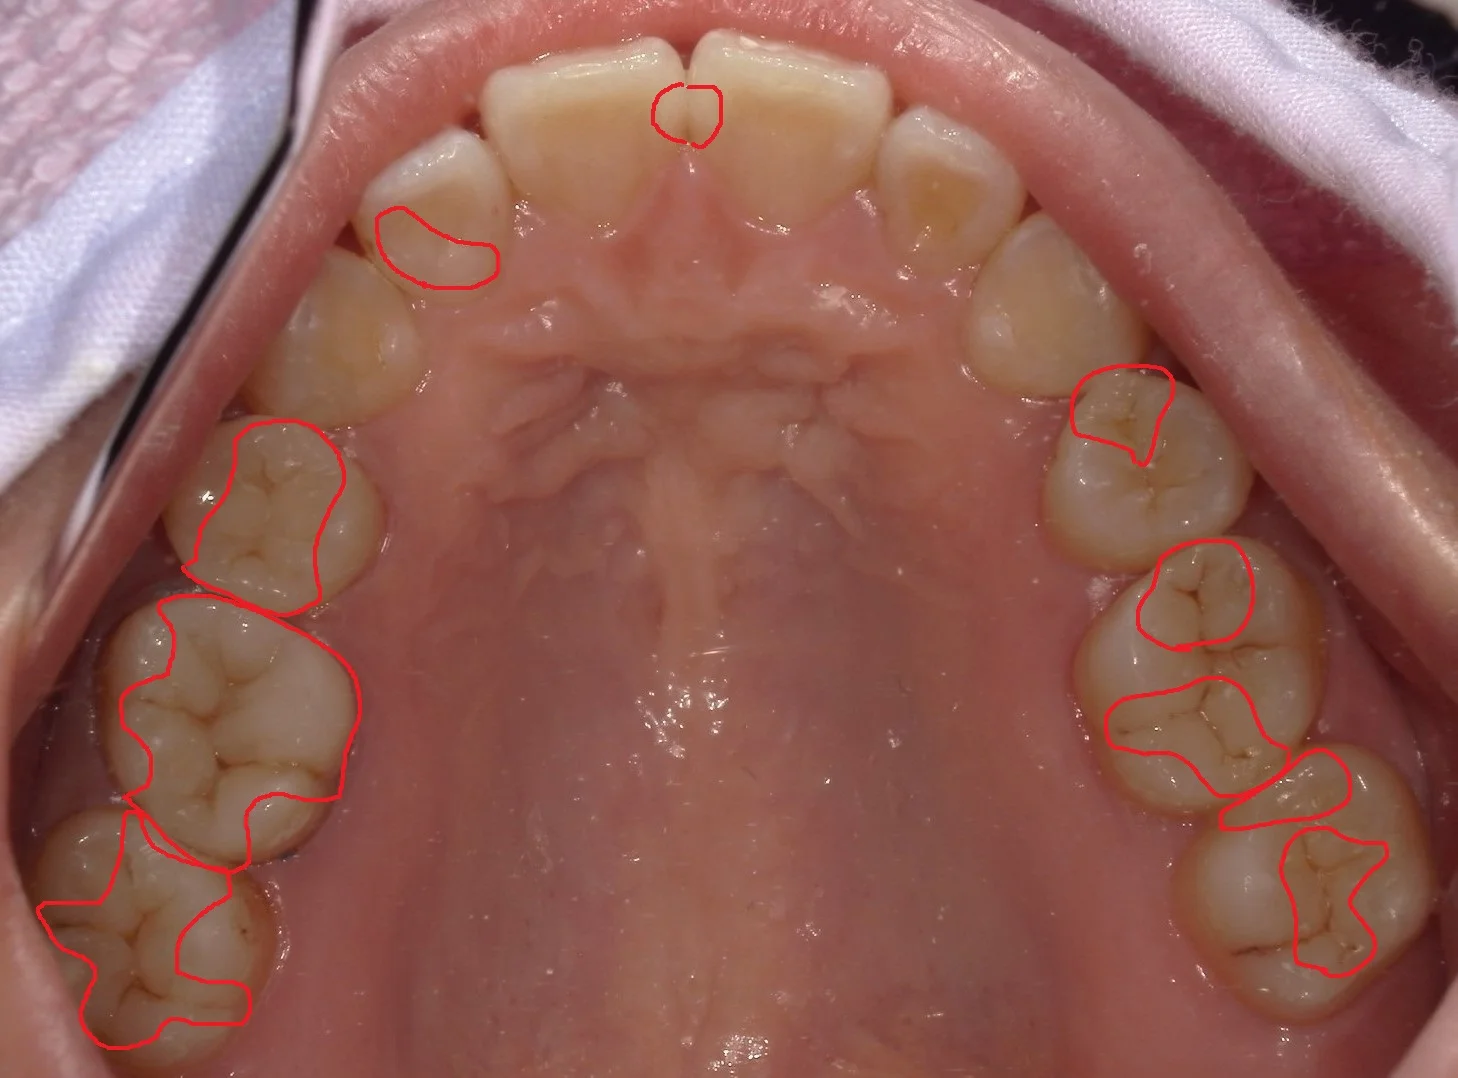

上下左右全ての部分の虫歯をセラミックを用いずにダイレクトボンディングにて治療した方のお写真を許可を頂きましたので、アップさせていただきます。

ちょっとしたクイズ形式でやってみましょうか。

どこを治療したでしょうか?!

分かりますかね?

結構歯科医師の方々に同じ質問しても分からない方がほとんどでした!

では、答えは下の方に載せますので、スクロールしていってくださいね。

正解はこちらです!

結構たくさんの数を治してました!